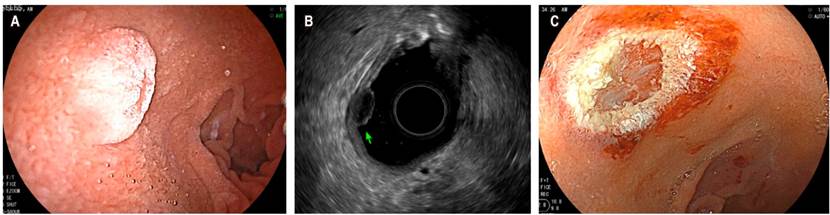

Otra indicación actual del USE es en la caracterización de lesiones subepiteliales, en las que se evalúa su profundidad para definir resecciones endoscópicas. En la Figura 3 se observa un tumor neuroendocrino de la segunda ecocapa donde se realiza mucosectomía con fines curativos.

En las lesiones de la pared gastrointestinal se logran identificar las 5 ecocapas principales: la primera y segunda (mucosa que incluye la capa muscular de la mucosa), la tercera (submucosa), la cuarta (la capa muscular propia) y la quinta (serosa o adventicia) (Figura 2 A). También permite la medición del tamaño de la lesión y la evaluación de cualquier linfadenopatía asociada para su posterior estadificación. En el grupo de lesiones que tienen un riesgo potencial de malignizarse se encuentra el tumor del estroma gastrointestinal (GIST) y la mayoría de estos son gástricos (constituye entre el 60 % y 70 % de todos los casos) (Figura 2 B), 20 %-30 % se ubican en el intestino delgado y un poco menos del 5 %, en el esófago. Respecto al diagnóstico de GIST, el objetivo de la obtención de tejido es recoger material que demuestre células fusiformes, además de la realización de inmunohistoquímica (IHQ). En la IHQ se recomienda realizar las tinciones de CD117, DOG1, S100, CD34 y PDGFRA; con estas se logra diferenciar de forma adecuada el GIST de otras lesiones subepiteliales 8. Tradicionalmente, la punción/aspiración con aguja fina USE-guiada (USE-PAAF) ha sido el método para obtener tejido. El rendimiento diagnóstico es muy variable (entre 46 % y 93 %) y, en general, es limitado porque el tamaño de muestra podría ser insuficiente para realizar IHQ. En un estudio multicéntrico reciente se compararon la biopsia con aguja fina (USE-BAAF) frente al USE-PAAF en el rendimiento en la obtención de muestras para citopatología, en la capacidad de obtener un diagnóstico basado en IHQ y el rendimiento diagnóstico definitivo. Los resultados en muestras de citopatología fueron de 92 % frente a 46 % (p = 0,001), 89 % frente a 41 % en IHQ (p = 0,001) y 89 % frente a 37 % en diagnóstico definitivo (p = 0,001) entre los grupos BAAF frente a PAAF, respectivamente. Los autores concluyen que el USE-BAAF es superior al USE-PAAF en el rendimiento diagnóstico histológico del GIST 9.